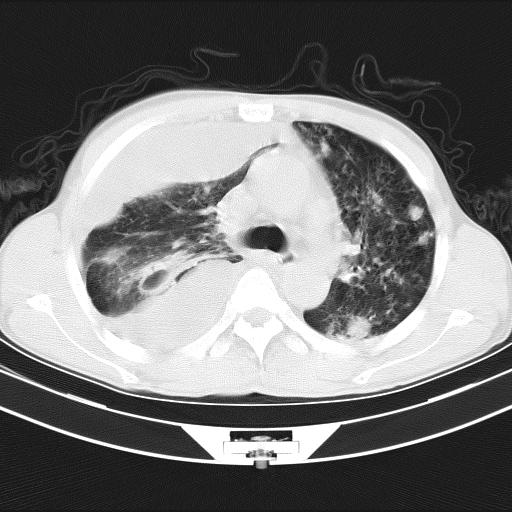

男性,44岁,结核病史多年。现胸闷气短,咳嗽,偶咳血。

1、右侧大量胸腔积液伴右肺压缩性膨胀不全,建议抽液治疗后复查 2、两肺继发性tb伴空洞形成。

1)两肺继发性肺结核伴空洞形成,左肺多发性结核球。2)右侧大量胸腔积液伴右肺部分膨胀不全。3)纵隔淋巴结肿大。

吉大一院胸水抽检结果:结核性胸水

结核性胸水——结核性胸膜炎 感谢楼主反馈结果